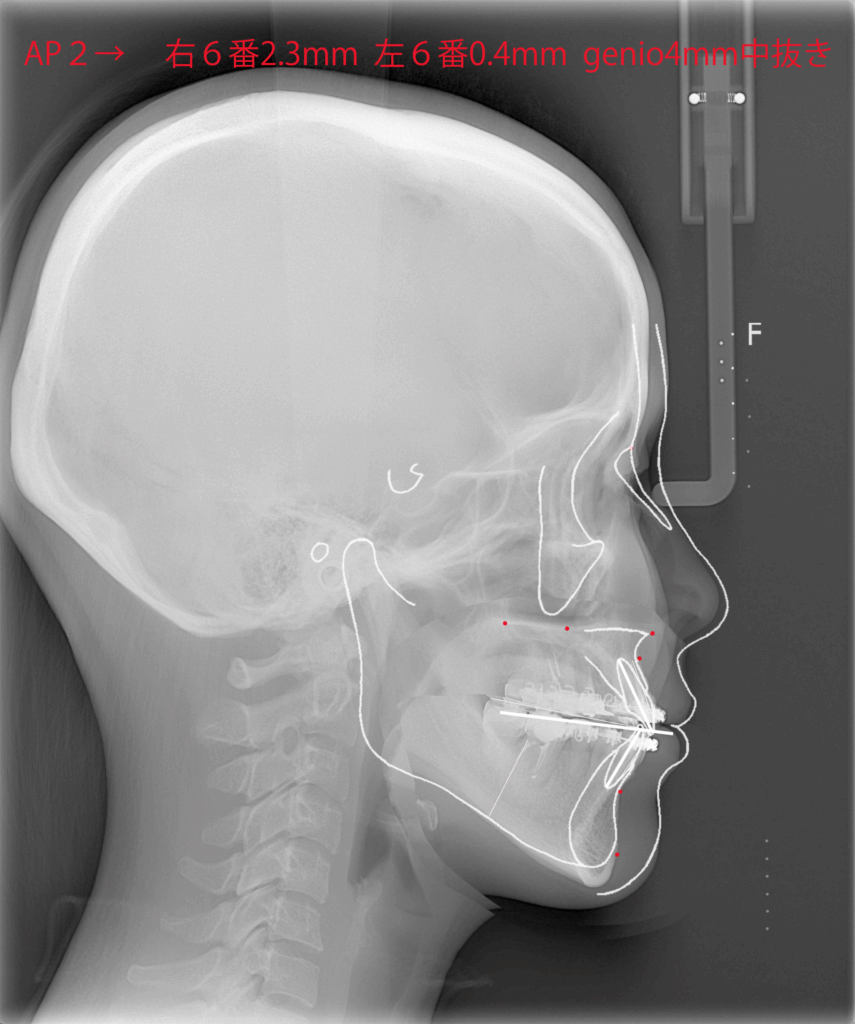

レントゲンを用いて骨格の特徴を把握します。白線の輪郭は標準的な骨格を表しています。標準骨格と比べると、下顎が前に出ていて、なおかつ垂直方向に長いことがわかりました。

下顎はSSROで後方に移動させ、上顎は鼻下の陥没感を改善するために上顎前歯の先端を回転中心として時計回転させて鼻下の骨を前方に出す計画としました。顎先は中抜きオトガイ形成で垂直方向の長さを短縮することにしました。

白線の標準骨格に一致するように骨の移動量を決めていきます。上顎は鼻下で2mm前進し、臼歯部で2mmほど上方に移動させます。全体として上下顎は時計回転することになります。顎先は4mmの中抜き短縮です。